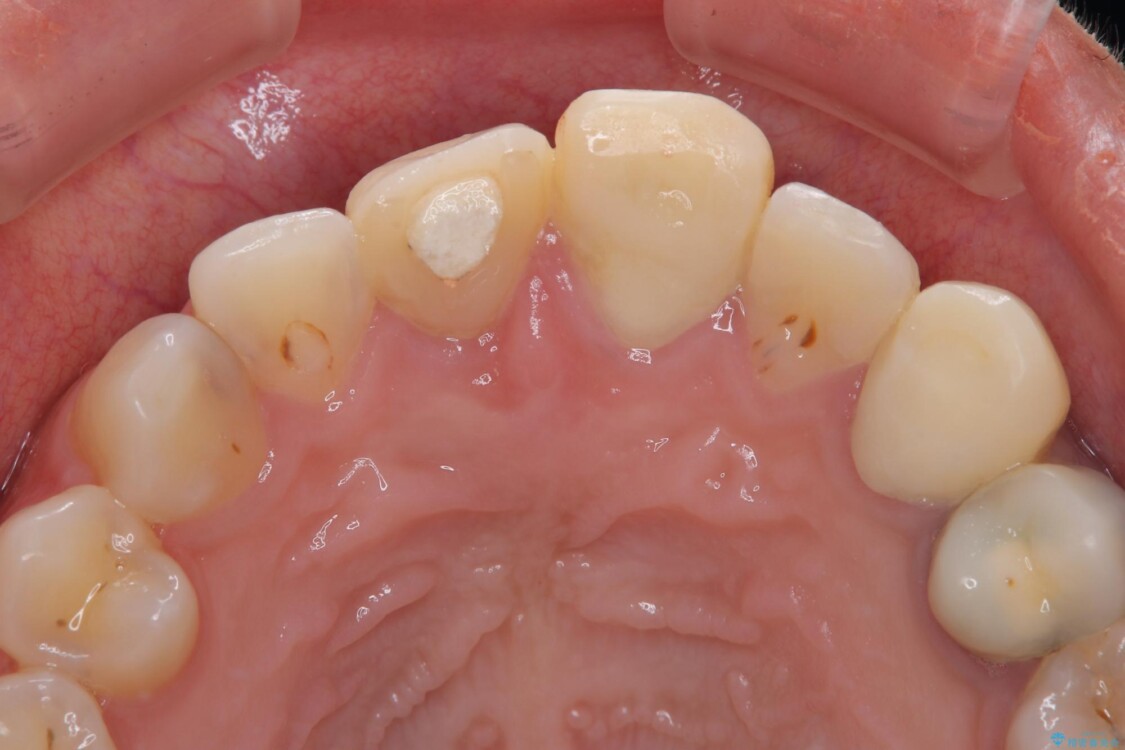

20代女性の患者様。 他院にて「上の前歯(右上中切歯)は抜歯してインプラントかブリッジにする必要がある」と診断され、大変ショックを受けられていました。 すでに根管治療を受けた歯でしたが、急に担当医が変わり、「抜歯が必要」とだけ説明されたことに不安感を抱き、当院を受診されました。 左上中切歯と犬歯も仮歯のままで、将来への不安が大きかったご様子です。

精密検査の結果、右上中切歯には**フェルール(歯の周囲の健全な歯質)**がほぼ存在せず、このままの状態での保存は困難と判断しました。

治療前

• 「抜歯してブリッジ」と言われた20代女性が選んだ治療とは|たった4か月で自然な笑顔に抜歯即時インプラント+審美補綴の症例 治療前画像